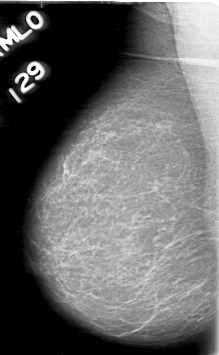

D_4055_1.RIGHT_MLO

D_4055_1.RIGHT_CC

RIGHT_CC LINES 5266 PIXELS_PER_LINE 3106 BITS_PER_PIXEL 12 RESOLUTION 43.5 NON_OVERLAY

RIGHT_MLO LINES 5311 PIXELS_PER_LINE 3271 BITS_PER_PIXEL 12 RESOLUTION 43.5 NON_OVERLAY